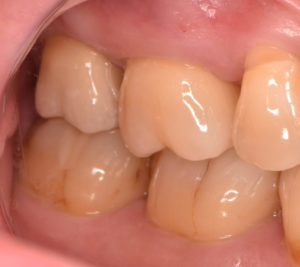

治療方法:不良補綴物を除去した後、う蝕を除去・隔壁形成した後ラバーダム防湿下にて根管治療を行った。根管内の感染物質を除去した後、通法に従い根管充填した。根尖病変の経過観察を行った後、ジルコニアセラミッククラウンにて歯冠修復を行った。その他全顎的な虫歯治療や歯周治療も行った。

費用:ジルコニアセラミッククラウン 170,500円(支台築造、プロビジョナルクラウン含む)

すでに根管治療がされているの歯の再治療例になります。再根管治療の目的は、根管内の感染物質を取り除くことにあります。精度の良いジルコニアセラミッククラウンでの再修復により、根管内に再度感染源が侵入するのを防ぎ、根尖病変の再発を防ぐことで長く歯を使用することが可能となります。